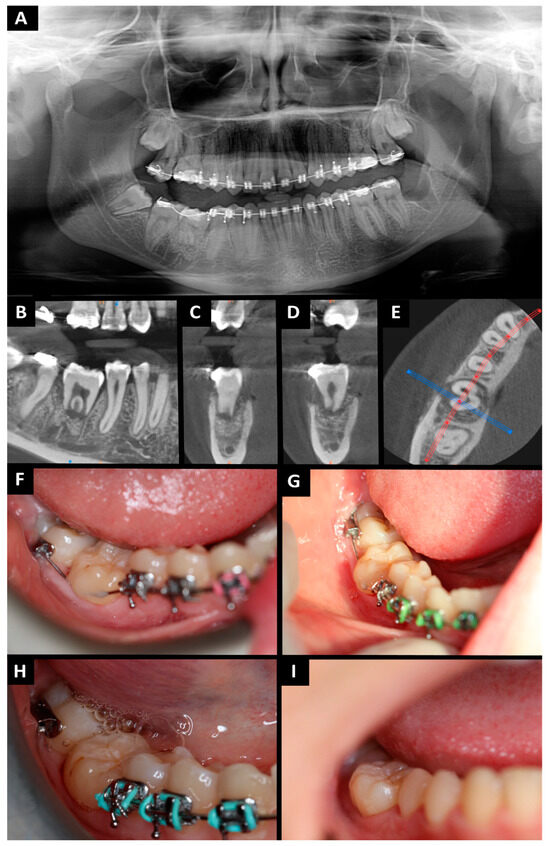

2. Case Presentation